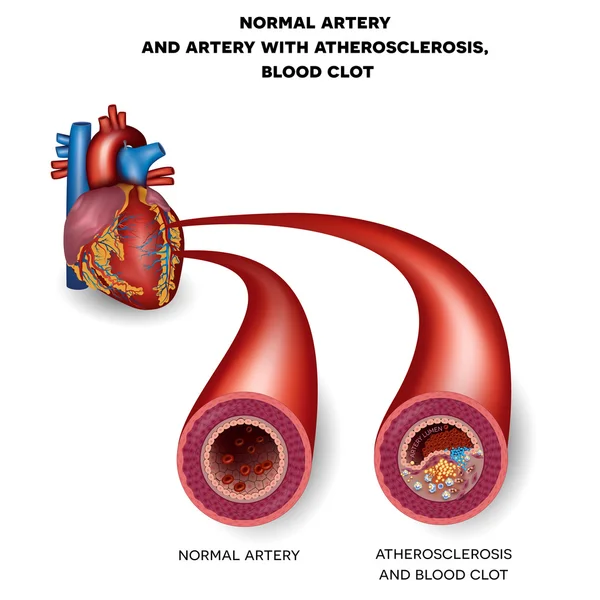

The Warning Signs Of Clogged Arteries Heart Blockage Clogged

Clogged Arteries Scientific Animations